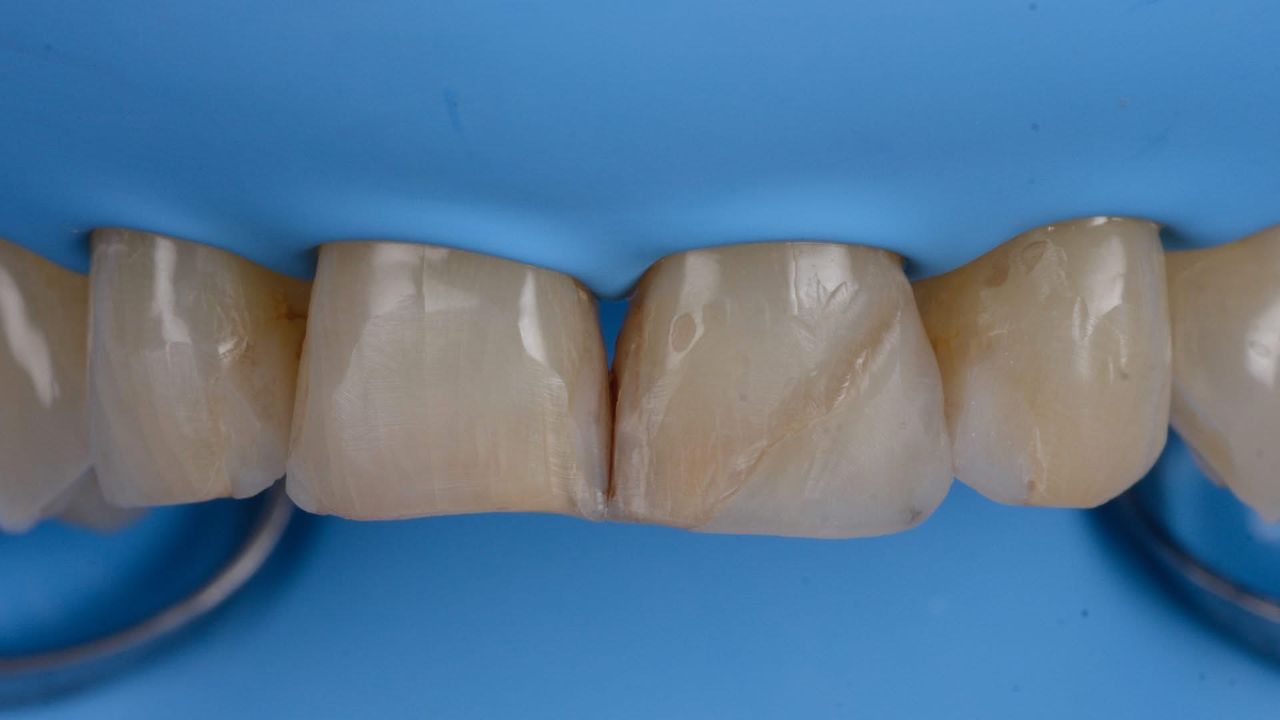

• Odontología estética

Fotos y videos

Muy buena atención, honestamente nunca me había sentido igual y con tanta seguridad en manos del odontólogo! Súper tratamiento de carillas

• DR EDUARDO HUERTA RAMÍREZ Carillas  •